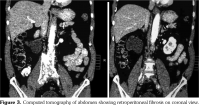

On investigations, his complete blood count was normal. Erythrocyte sedimentation rate was 88 mm in first hour. Random blood sugar was 93 mg/dL. His serum urea was 26 mg/dL and serum creatinine was 1.1 mg/dL. Liver function tests were within normal limits. Chest X-ray revealed non-homogenous opacities in bilateral lung fields. Pulmonary function tests revealed forced expiratory volume in one second (FEV1) of 61% and forced vital capacity (FVC) of 73%. FEV1/FVC ratio was 84%. Two-dimensional echocardiography was within normal limits. Ultrasonography of the abdomen revealed small-sized right kidney (6.9x2.9 cm) with dilated pelvi-calyceal system and dilated proximal ureter. Computed tomography (CT) of the abdomen revealed medial deviation of right ureter and presence of retroperitoneal soft tissue along infra-renal aorta and peri-caval area with calcification extending up to iliac vessels suggestive of RPF (Figures 1, 2, 3, and 4). High-resolution CT of the chest confirmed presence of interstitial lung disease (ILD). ANA profile (ENA) revealed that anti-U1 snRNP was strongly positive. Rest of the autoantibodies were negative. His serum immunoglobulin G levels were within normal limits. Thus, we arrived at a diagnosis of MCTD with RPF and ILD. He was started on mycophenolate 720 mg twice daily, hydroxychloroquine 200 mg once daily and deflazacort 6 mg once daily for MCTD, pirfenidone 400 mg twice daily for ILD and tamoxifen 20 mg once daily for RPF. On follow-up at six months, he was doing physically well. His symptoms of cough were reduced and dyspnea improved from NYHA class IV to class II. Repeat pulmonary function tests revealed FEV1 of 59%, FVC of 71% and FEV1/FVC ratio of 84%. However, repeat ultrasonography of the abdomen did not reveal any significant change in pelvi- calyceal system.

In 1972, Sharp et al.,[1] recorded a group of patients who had clinical features of SLE, SSc and PM with high titers of anti-extractable nuclear antigen antibody. They published it as a new disease entity: MCTD. Since then, there has been an increasing number of classification criteria published for the diagnosis of MCTD, namely, Kasukawa et al.[3] Alarcon-Segovia and Villareal[4] and Kahn and Appelboom.[5] There has been no consensus on clinical features owing to varied manifestations and frequent overlap of symptoms with other autoimmune conditions. However, high titers of antibodies against U1 snRNP have been found in most patients.[6] Our patient had symptoms of dysphagia, epistaxis and ocular sicca coupled with high titers of anti-U1 snRNP which led us to the diagnosis of MCTD. He also had pulmonary involvement in the form of ILD. One study showed 47% of cases of MCTD to have ILD.[7] The most frequent histological picture seen is non-specific interstitial pneumonia, followed by usual interstitial pneumonia and lymphocytic interstitial pneumonia.[8] RPF was first reported by Ormond[9] in 1948. It is a rare condition characterized by inflammation and fibrosis of the retroperitoneum, around the infra-renal portion of abdominal aorta and iliac arteries and usually entraps ureters and inferior vena cava.[10] A recent study reported incidence of RPF around 1.3 per 100,000 population per year in Netherlands.[11] The mean age of presentation is around 50 years with male predominance (2:1-3:1). Abdominal CT and magnetic resonance imaging are the investigations of choice for the diagnosis of RPF and they reveal a homogenous mass near the lower abdominal aorta and iliac arteries that surround and displace the ureters medially. Medical therapies for RPF include steroids, tamoxifen, other immunosuppresives such as azathioprine, mycophenolate and anti-CD20 antibody such as rituximab. In one single-center prospective observational study of 55 patients with RPF treated with tamoxifen monotherapy for a minimum of two years, 47 (85%) patients reported substantial resolution of symptoms after a median treatment duration of three weeks. There was a mass regression in 39 (71%) patients at four months and 47 (85%) patients at eight months of follow-up, respectively. Recurrence- free survival in patients with treatment success after post-treatment follow-up of 21 months was 68%.[12] To our knowledge, there is no previously published case report on presence of RPF in a patient of MCTD. This is indeed a rare occurrence.